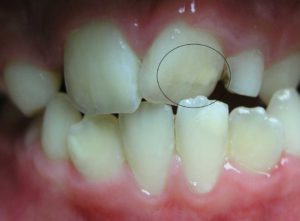

Якщо ви помітили у дитини на зубі після його прорізування плями – мерщій до стоматолога. Найчастіше вони білого кольору, проте можуть бути і жовтуваті, і коричневі, а у важких випадках навіть із дефектами та “ямками” на зубі.

Однин з можливих варіантів у цьому випадку – гіпоплазія емалі. Це недорозвиток емалі зуба внаслідок порушення її мінералізації, ще до моменту прорізування. У такому випадку головне – не допустити процесу руйнування зуба в подальшому. Тому для лікування застосовують спеціальні покриття, які насичують емаль необхідними мінералами та відновлюють її структуру. При важких формах із зміною кольору та форми зуба – можливе вибілювання або естетична реставрація.